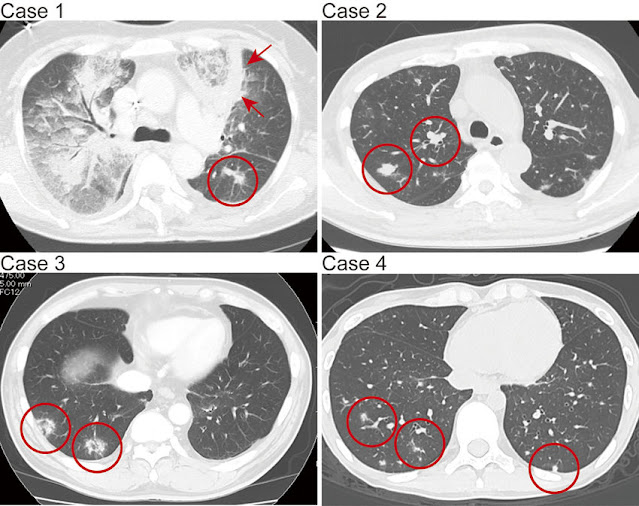

CT nalaz (slike su sa interneta)Dijagnoza:

Laboratorija, biopsija i CT pregled